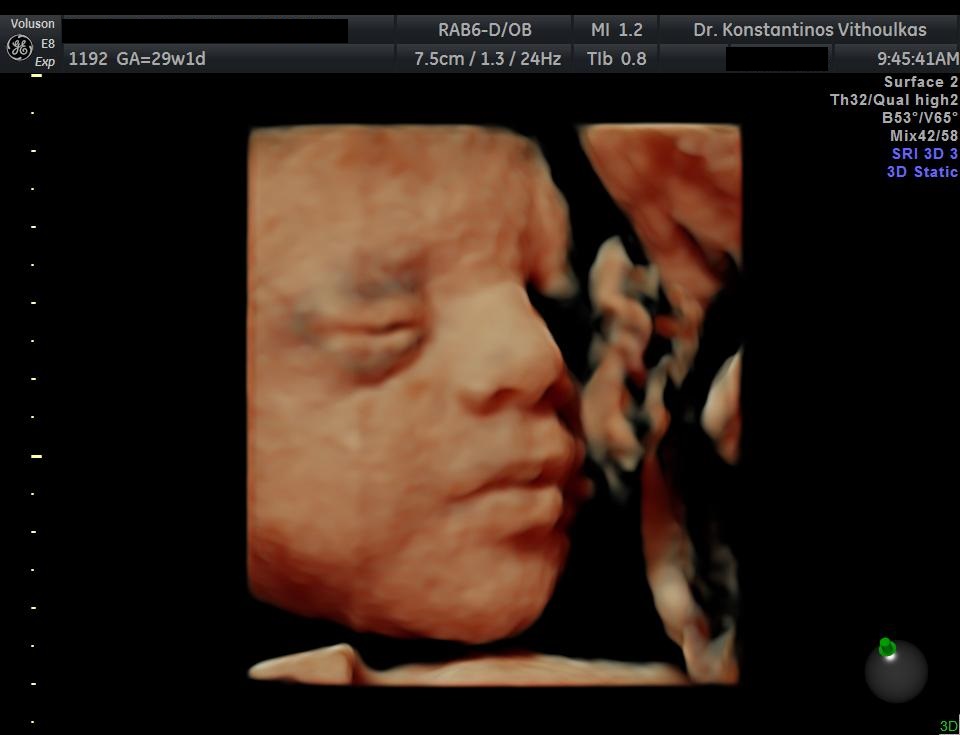

Φωτογραφίες από το αρχείο και από το χώρο του ιατρείου του γυναικολόγου Βυθούλκα Κωνσταντίνου, καθώς και του εργαστηρίου της κυτταρολόγου Λιβέρη Κατερίνας.